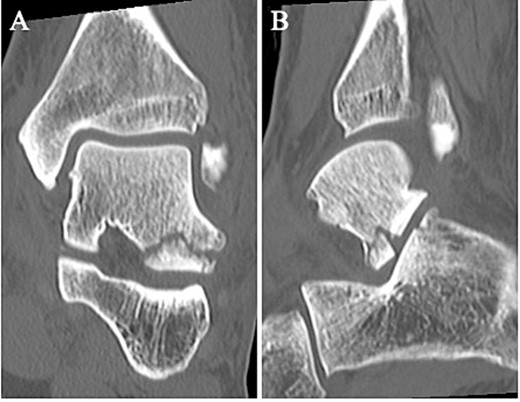

The surgery was performed under general anesthesia in the lateral position, with the affected side up. A thigh air tourniquet and a fluoroscopy were used. First, 3 ml of normal saline was injected into the sinus tarsi. A viewing portal was then made above the sinus tarsi, and a working portal was made 2 cm anterior to the viewing portal. A 30° arthroscope with a diameter of 2.7 mm was used to observe the fracture site (Fig. 3A). The synovium, adipose tissue and coagulation clot surrounding the fracture site were removed with a 3.0-mm-diameter motorized shaver, and the bone fragment was reduced using a guidewire sleeve and fixed with a 0.8-mm guidewire (Fig. 3B), the fragment was fixed through the guidewire with a cannulated double-threaded screw (Double Thread Screw Japan Mini, Meira, Nagoya, Japan) (Fig. 3C). After confirming that the bone fragment was fixed in the correct position under a fluoroscopy, the wound was sutured, and so the surgery was concluded (Fig. 4).

(A) A 30° arthroscope with a diameter of 2.7 mm was used to observe the fracture site. (B) The bone fragment was reduced using a guidewire sleeve and fixed with a 0.8-mm guidewire. (C) The fragment was fixed through the guidewire with a cannulated double-threaded screw.